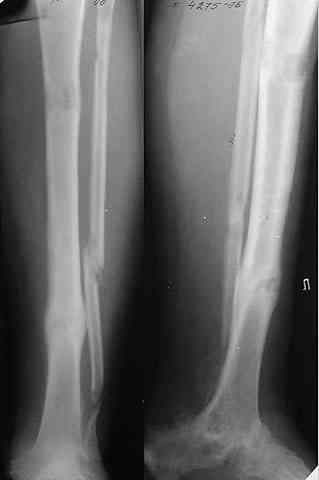

Глубокоуважаемые коллеги! Просим совета в лечении пациента с последствиями тяжелой сочетанной травмы. Пациент С., 41 года, по профессии бизнесмен, в сентябре 2005 г. пострадал в дорожно-транспортном происшествии (упал с мотоцикла). Диагноз: ЗЧМТ, ушиб головного мозга тяжелой степени. Открытый переломо-вывих левой таранной кости. Закрытые переломы лонной и седалищной костей слева. Был доставлен в НИИСП им. Н.В. Склифосовского. При ПХО раны выявлен открытый перелом левой таранной кости (III тип по Hawkins) с утратой вывихнутого тела таранной кости. Выполнена ПХО, фиксация голени и стопы стержневым аппаратом. Рана зажила без осложнений. Аппарат демонтирован через 1,5 месяца. В настоящее время больной предъявляет жалобы на боль в голеностопном суставе при нагрузке. Передвигается с опорой на костыли с дозированной нагрузкой на левую стопу.Голень и стопа фиксированы циркулярной пластиковой повязкой. Сохраняются остаточные явления ЧМТ (в виде сниженной критики к своему состоянию и определенной недисциплинированности в выполнении врачебных рекомендаций) Рентгенограммы – рис. 1, 2 (просим извинения за низкое качество рентгенограмм), схема – рис. 3. В качестве варианта хирургического лечения мы считаем возможным выполнить следующее вмешательство: артродез большеберцовой и пяточной костей в сочетании с артродезом переднего края большеберцовой кости и головки таранной кости с фиксацией спонгиозными винтами. Считаем выполнение артродеза переднего края большеберцовой кости и элементов I луча стопы необходимым для максимального восстановления опороспособности конечности. Однако выполнение операции в указанном объеме привело бы к относительному укорочению внутреннего свода стопы. Мы видим два пути решения данной проблемы: Вариант 1. Применение костного трансплантата (свободного или на сосудистой ножке) для замещения дефекта головки таранной кости и сохранения геометрии внутреннего свода стопы (рис 4). Преимущество: относительная простота операции. Недостаток: высокий риск замедленной консолидации или лизиса трансплантата. Вариант 2. Резекция участка пяточной кости с последующим остеосинтезом винтами для укорочения наружного свода стопы (рис 5, 6). Преимущества: сохранение собственного кровоснабжения всех синтезируемых участков костей. Недостатки: дополнительная травматизация, усугубление деформации стопы в виде нарушения наружного свода. Будем признательны за ваши предложения, включая возможные альтернативные варианты лечения.Заранее благодарны за добрые советы и поддержку. А. Федосов, О. Диденко, П. Иванов. Отделение множественной и сочетанной травмы НИИСП им. Н.В. Склифосовского, г. Москва.

Не адресована другая проблемы - берцово-пяточный блок достигается ценой укорочения конечности на 3-4 см. Поэтому надо предусмотреть что-то для удлинения. У нас в клинике традиционный подход - билокально удлинять большеберцовую кость. Раньше еще и малоберцовую рубили на двух уровнях. Сейчас (спасибо коллегам из форума) пользуемся только

той остеотомией, которая делается для отворачивания кожно-костного лоскута с малоберцовой костью. Фиксируем все это аппаратом (пример в приложении) около 4 мес.